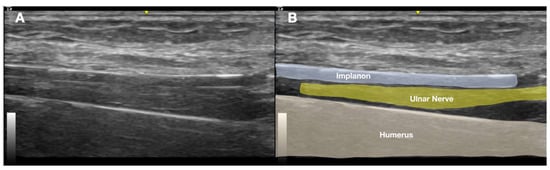

2.1. Prior Imaging Included Radiography (Figure 3), Which Confirmed the Implant’s Location, and Ultrasound (Figure 4), Which Demonstrated Its Proximity to the Ulnar Nerve